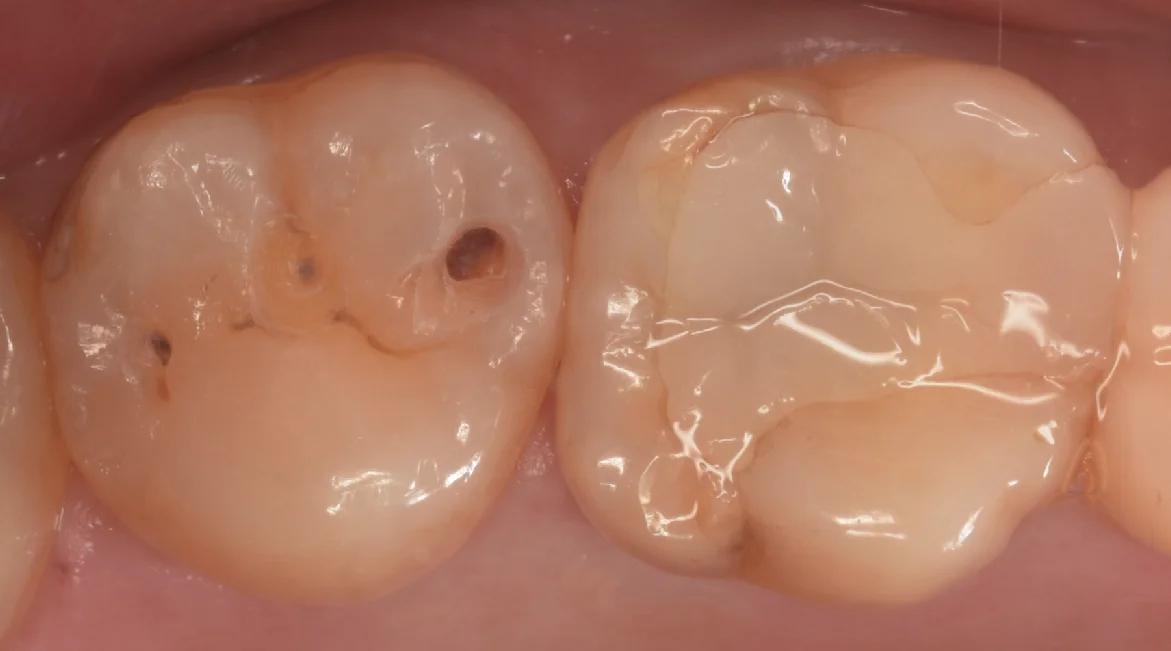

軽く虫歯を見えやすくしたのがこちらになります。

中心の白い詰め物のところはそこまで虫歯ではなかったですね。

右側の方の虫歯が一番大きい状態です。

左側の虫歯は非常に小さい状態でしたね。